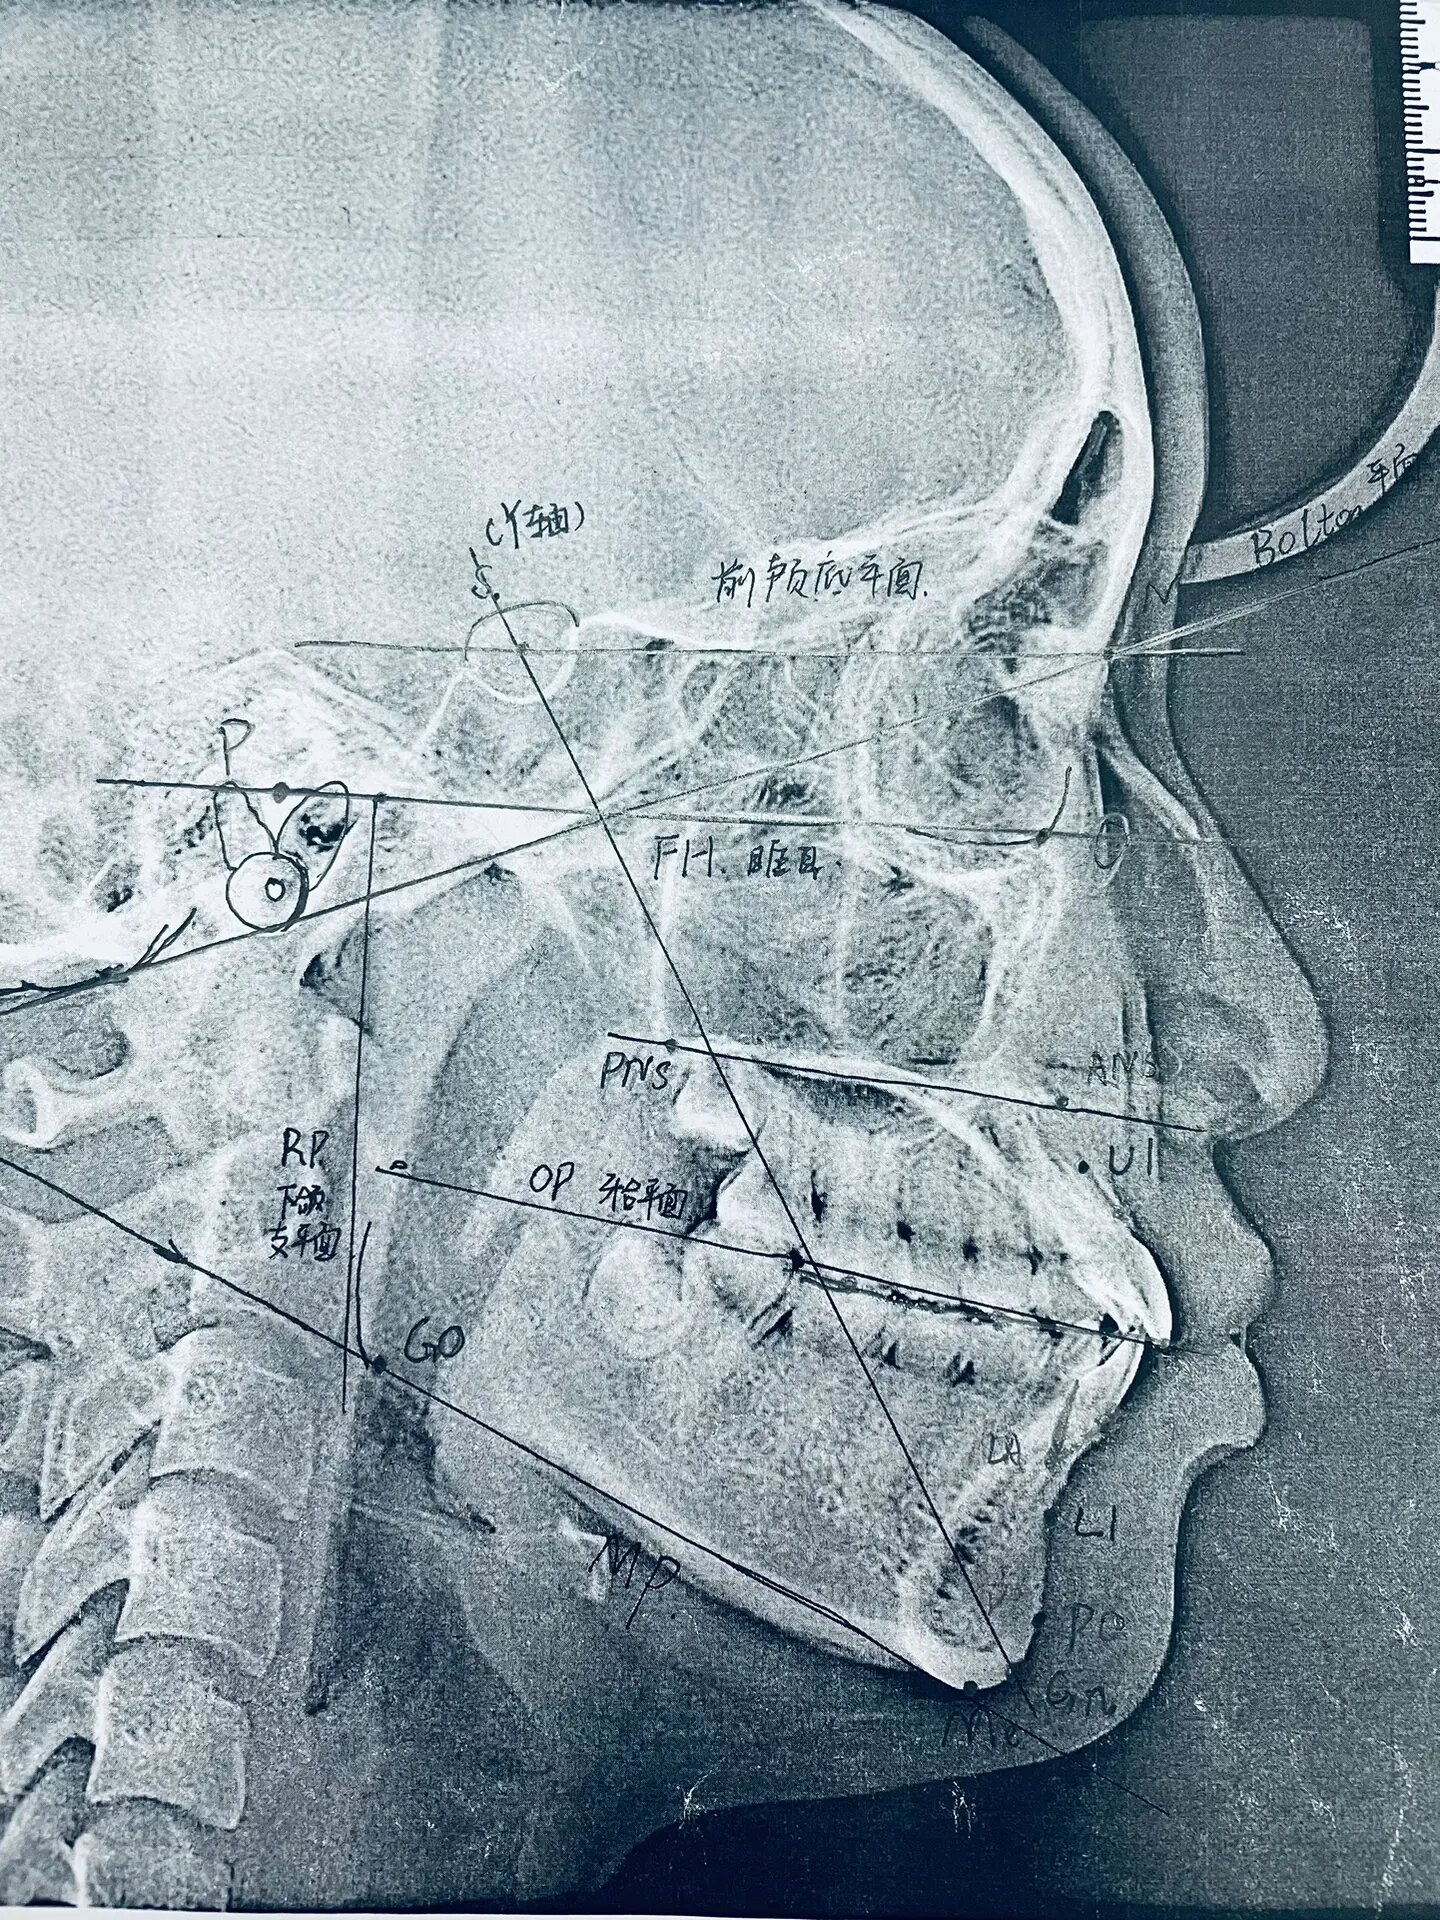

口腔 / 我和口腔科的故事(8): 北大口腔正畸篇-x线头影测量图解